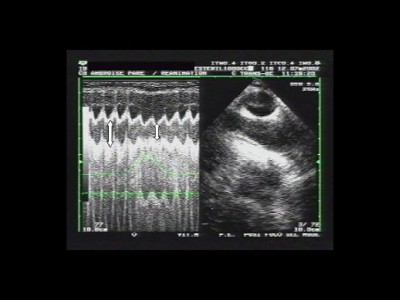

Figure 1 : Le signal de pression dans les voies aériennes apparaît en vert sur l'écran.

Les diamètres maximal et minimal sont notés avec les flèches.